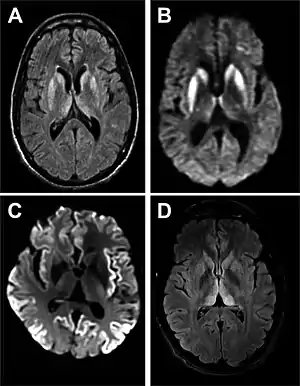

Magnetic resonance image of sporadic CJD[2]

Brain MRI is the most useful imaging modality for changes related to CJD. Of the MRI sequences, diffuse-weighted imaging sequences are most sensitive. Characteristic findings are as follows:

dwMRI, FDG PET and post mortem histology from a patient who presented with sCJD aged 66

• Focal or diffuse diffusion-restriction involving the cerebral cortex and/or basal ganglia. In about 24% of cases DWI shows only cortical hyperintensity; in 68%, cortical and subcortical abnormalities; and in 5%, only subcortical anomalies.[44] The most iconic and striking cortical abnormality has been called "cortical ribboning" or "cortical ribbon sign" due to hyperintensities resembling ribbons appearing in the cortex on MRI.[45] The involvement of the thalamus can be found in sCJD, is even stronger and constant in vCJD.[46]

• Varying degree of symmetric T2 hyperintense signal changes in the basal ganglia (i.e., caudate and putamen), and to a lesser extent globus pallidus and occipital cortex.[42]

• Cerebellar atrophy

Brain FDG PET-CT tends to be markedly abnormal, and is increasingly used in the investigation of dementias.

• Patients with CJD will normally have hypometabolism on FDG PET.[47]